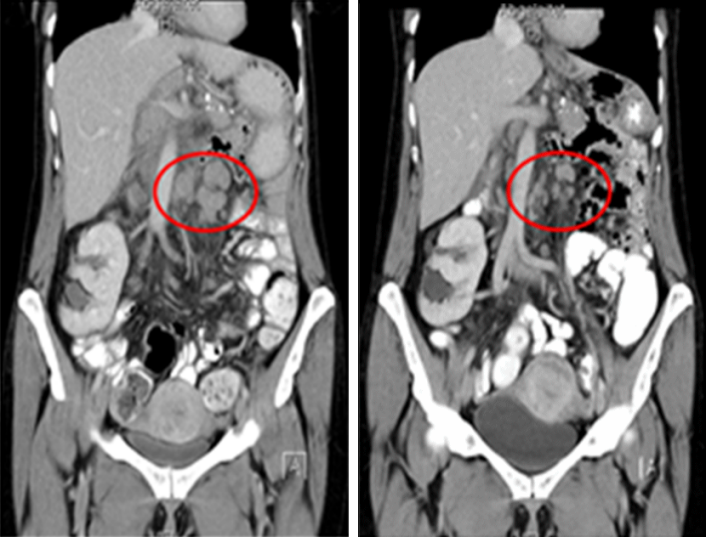

Schon nach 1. Gabe deutliches Ansprechen (partielle Remission der zervikalen und intraabdominellen Lymphknoten-Metastasen, s. Abbildung 2 [Abb. 2]). In 07/2017 onkologische Rehabilitation in der Paracelsus-Klinik Scheidegg (dort Fortsetzung der Therapie/7. Gabe Pembrolizumab). Die Therapie wurde unverändert ohne subjektive Nebenwirkungen gut vertragen, die Patientin wollte nach der Rehabilitation wieder ihre Arbeit als Lehrerin aufnehmen.

Abbildung 2: Ergebnis der radiologischen Verlaufskontrolle (CT-Abdomen) bei Patientin Nr. 1 nach 4 Gaben Pembrolizumab (partielle Remission der paraaortalen Lymphknotenmetastasen)

Bei guter Verträglichkeit ohne subjektive Nebenwirkungen Eingliederung ab September 2017. Telefonat Ende 10/2017 sowie in 07/2018: Patientin hat die Eingliederung abgeschlossen, unverändert gutes Ansprechen (partielle Remission) und gute Verträglichkeit der seit 1½ Jahren durchgeführte Immuntherapie mit Pembrolizumab.